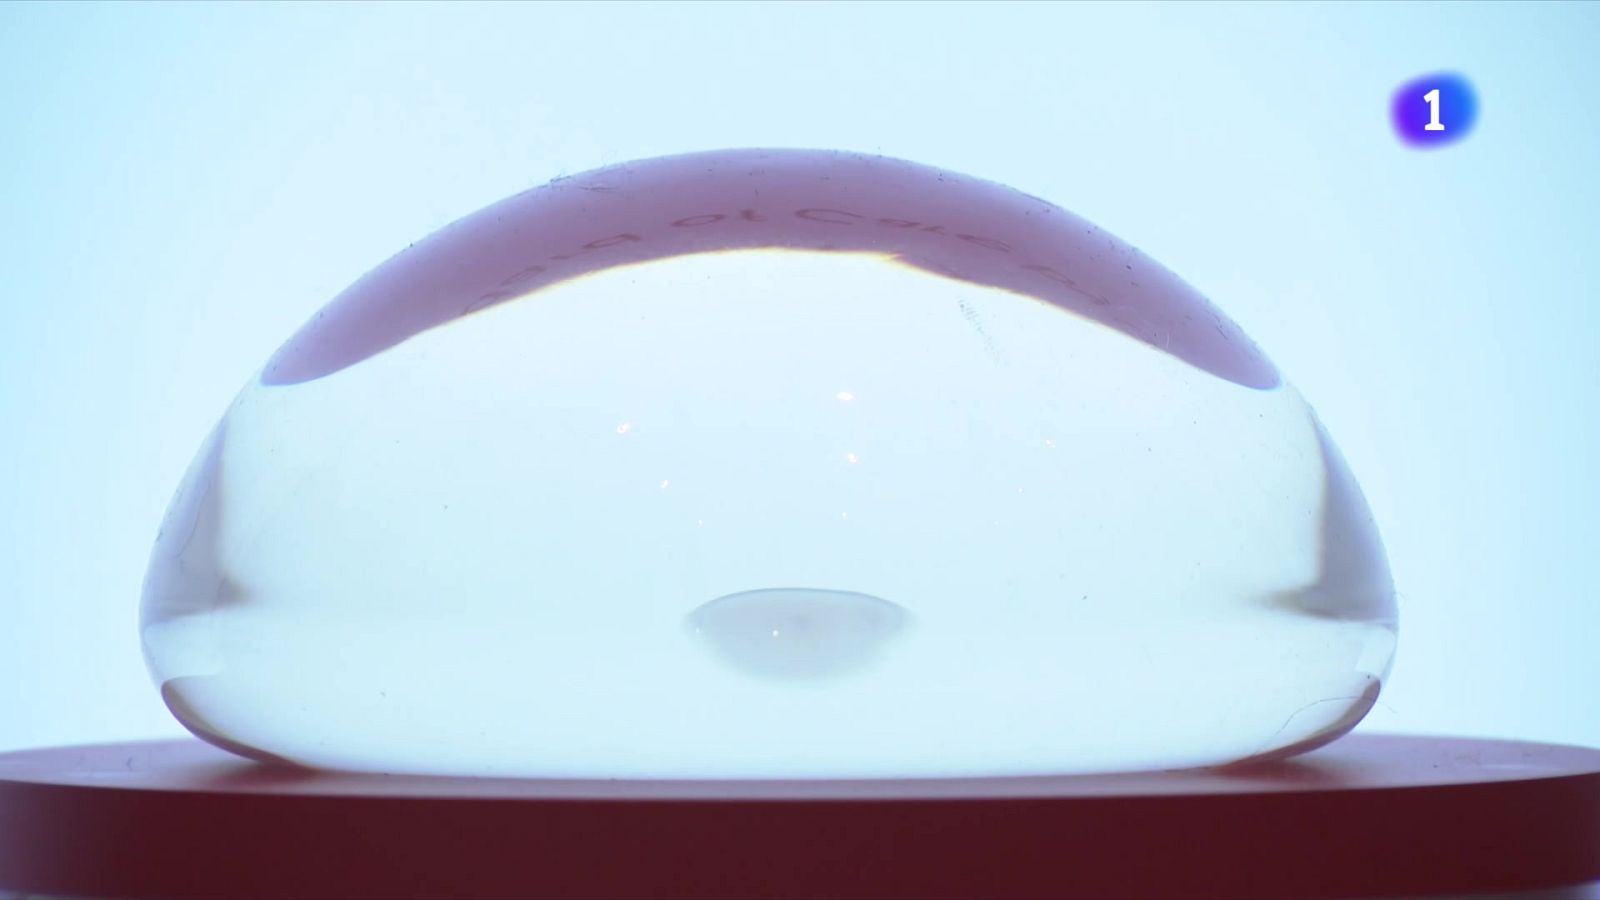

Les explantacions de pròtesis mamàries es dupliquen a Espanya en els últims 8 anys

L’envelliment dels implants i les malalties derivades del seu desgast, principals motius de l’augment de les extraccions